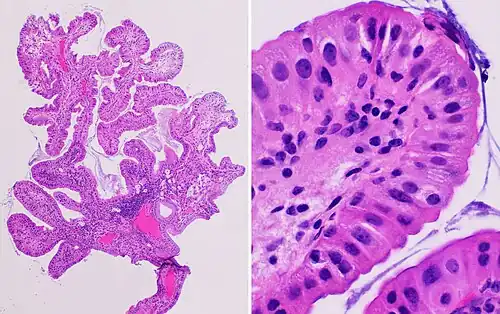

Histopathology of a hyperplastic polyp: There is no dysplasia.

Histopathology of a hyperplastic polyp: There is no dysplasia.